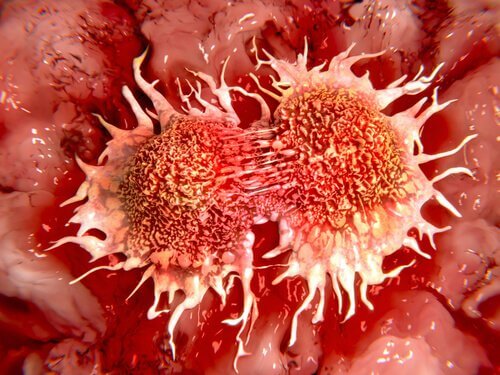

Una scoperta fa luce su come le cellule cancerogene differiscono da quelle sane e potrebbe portare allo sviluppo di nuove strategie per l’intervento terapeutico per i tumori difficili da trattare in futuro.

“Abbiamo scoperto che il cancro al seno, la leucemia, il linfoma e le cellule di neuroblastoma hanno troppe pause PIP che alterano la funzione proteica. La scoperta aprirà una nuova strada allo sviluppo di farmaci che bloccano la formazione del segnale di stop PIP da parte degli enzimi della chinasi“, ha detto Michael Overduin, un ricercatore oncologico dell’Università di Alberta e Professore di biochimica che ha guidato il progetto di ricerca.

I campioni di pazienti oncologici presentano troppe pause PIP che potrebbero portare alla crescita non regolata osservata nelle cellule tumorali. Segnali PIP-stop simili sono stati trovati sovrautilizzati in un gran numero di altre proteine coinvolte in altri tipi di cancro, in cui potevano anche influenzare la crescita del tumore.